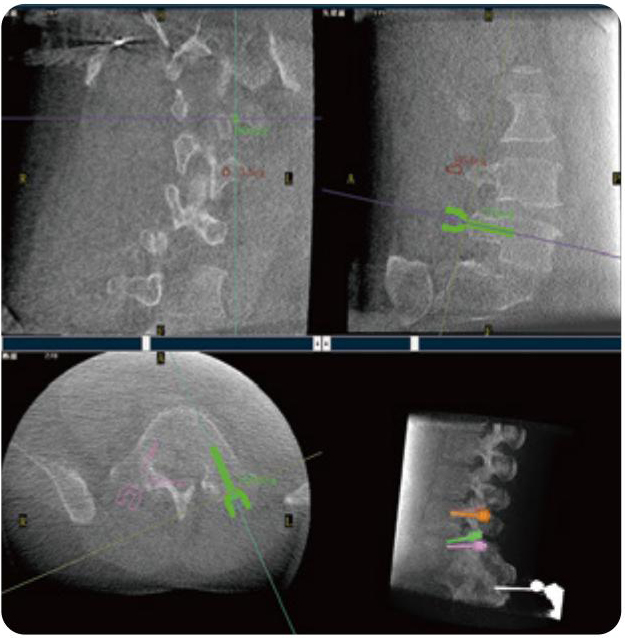

PL300B可應用于多節(jié)段脊柱外科手術,輔助醫(yī)生定位病灶部位,為脊柱外科手術(經(jīng)皮椎體成形術、椎弓根螺釘內固定術等術式)提供術前手術流程規(guī)劃、入釘位置、角度可視化引導,模擬仿真入釘輔助。

PL300B搭配普愛醫(yī)療自主研發(fā)生產(chǎn)的平板3D C形臂,借助一體化自適應配準( 軌跡配準)技術,通過追蹤C形臂三維采集軌跡,自動完成圖像坐標建立和系統(tǒng)坐標配準。配準精度更高,操作步驟少,系統(tǒng)運作效率高。